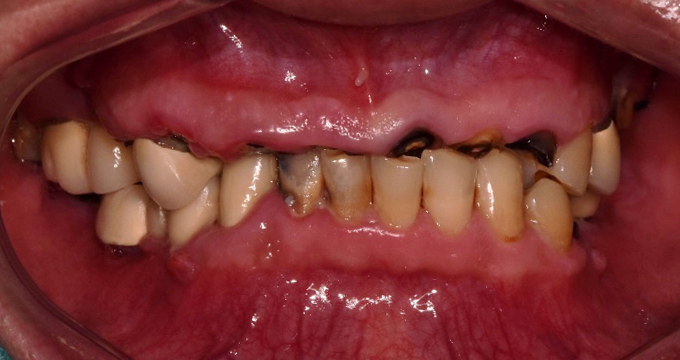

치료 전

40대 남성 환자분으로, 위 아래 치아들이 전체적으로 망가짐에 따라 얼굴의 '수직고경'이라고 하는 하안면의 높이가 줄어들어 있었습니다.

이러한 경우에 당일 1시간 내외의 검진과 상담으로 급하게 치료 결정를 하기보다 다음 내원까지 어떤 치아를 어떤 치료로 살릴지, 빼야만 하는지, 빼고 나서는 어떤 순서로 치료하는지 신중하게 치료 계획 세운 후 여러 단계를 걸쳐 치료를 진행하였습니다.